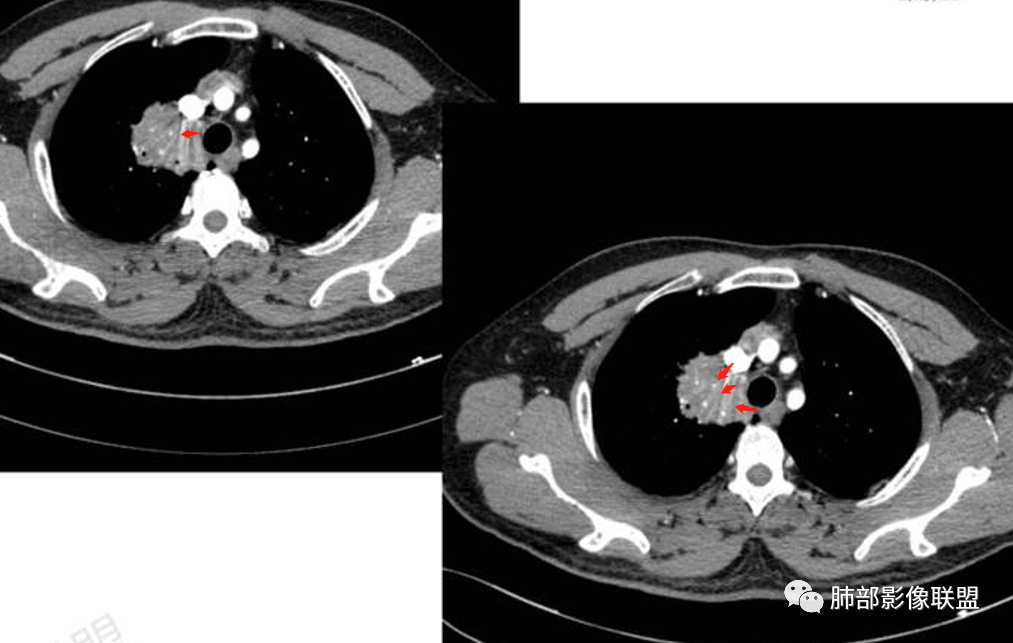

病理结果:MALT

肺内黏膜相关淋巴组织淋巴瘤(MALT)

黏膜相关淋巴组织(Mucosa associated lymphoid tissue, MALT)淋巴瘤是来源于黏膜相关淋巴 组织边缘带的低度恶性非霍奇金B细胞淋巴瘤。肺MALT淋巴瘤较为罕见,约占淋巴瘤的0.14%~1%,易被误诊为肺炎或肺癌。

MALT淋巴瘤这一概念最早由Isaacson和 Wright等于1983年提出,其可发生全身具有黏膜的器官或组织,最常见于胃肠道,其次为肺(15%)组织,病因不明,目前多认为与慢性感染、吸烟或自身免疫性疾病有关。肺MALT淋巴瘤是较为罕见的低度恶性肿瘤,多见于50-70岁,男女发病率无明显差异,或男性略多于女性。

MALT淋巴瘤影像表现为实变、结节及磨玻璃影,其中实变是其特点,胸膜下或支气管血管束节段性分布具有特征性,跨叶征较常见,这可能与肿瘤细胞进入血循环后往往又回到上皮黏膜部位,它们从一处黏膜到另一处黏膜,但不会到外周淋巴组织等有关。国外多名学者的影像-病理研究报道认为其病理学基础是由于肿瘤细胞沿支气管血管束周围间质及胸膜浸润生长,形成小叶间隔增厚、支气管血管束增粗等间质性改变,进一步浸润肺泡壁、充填肺泡腔。

①实变的出现率100%,多表现为两(89%)或单肺多发,密度均匀,与邻近胸壁肌肉的密度大致相等,少见钙化(15%),这与病灶内血管保持 完整,血供丰富,且肿瘤生长缓慢,对缺氧耐受好,不易坏死有关。边缘磨玻璃影或晕征具有特异性,其病理学基础是肿瘤细胞对小叶间隔、肺泡壁的淋巴瘤样浸润;

③扩张的充气支气管为其较特征性的表现,出现率约为89%,支气管管壁无破坏,支气管常扩张并达病灶的边缘,这与炎症性肺癌明显不同,其病理学基础是肿瘤起源于肺间质,肿瘤细胞沿着脏器解剖结构生长,周围增生的结缔组织牵拉导致支气管扩张,因而这类支气管扩张在肿瘤治疗后有时可消失;

④血管造影征是另一 点,强化的肺血管形态及走行正常,无扭曲或增 粗,其病理学基础为肿瘤细胞沿间质增生浸润,不破坏血管或支气管,病灶内肺支架结构完整,本研究发现率为75%;

⑤病灶多为中度强化,部分轻度强化;

⑥肺门及纵隔淋巴结肿大少见;

⑧邻近胸膜多无增厚,部分胸膜下见清晰脂肪或少许积液可能具有一定特征性,既往国内外研究尚未报道此征象,本文认为其病理学基础可能为肿瘤细胞生长缓慢,多为间质淋巴瘤样浸润而不破坏脏器解剖结构,肺泡塌陷及周围纤维组织增生,可能致病灶牵拉邻近胸膜有关,这不同于文献;报道的机化性肺炎致邻近胸膜多条状水肿、增厚,此征象有助于二者的鉴别。